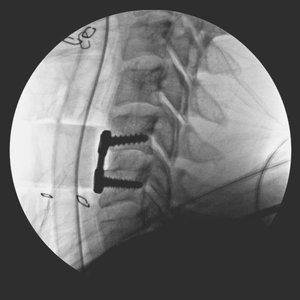

Anterior + Posterior Cervical Fusion [Trauma: DISH fracture]